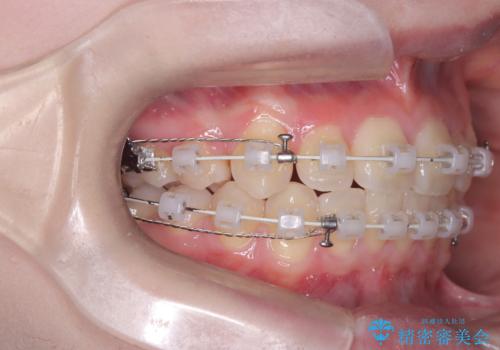

治療は、抜歯によって得られたスペースを活用し、前歯を後方へ移動させながら上下の中心を一致させる緻密な調整を行いました。

特に下顎の右方偏位に対しては、ワイヤーによる繊細なコントロールを行い、左右の咬合バランスを整えることに重点を置きました。2年半の治療期間を経て、突出していた前歯は理想的な位置に収まり、顎のズレも大幅に改善されました。